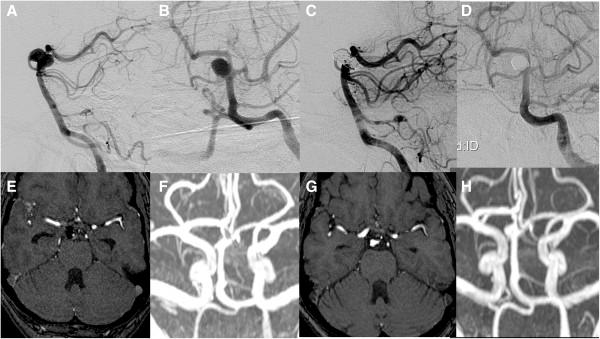

Subintimal hemorrhage in an unruptured superior cerebellar artery aneurysm: prelude to rupture: case report.

Neurosurgery. 2008 Aug;63(2):E368-9; discussion E369. doi: 10.1227/01.NEU.0000320423.40846.A1.